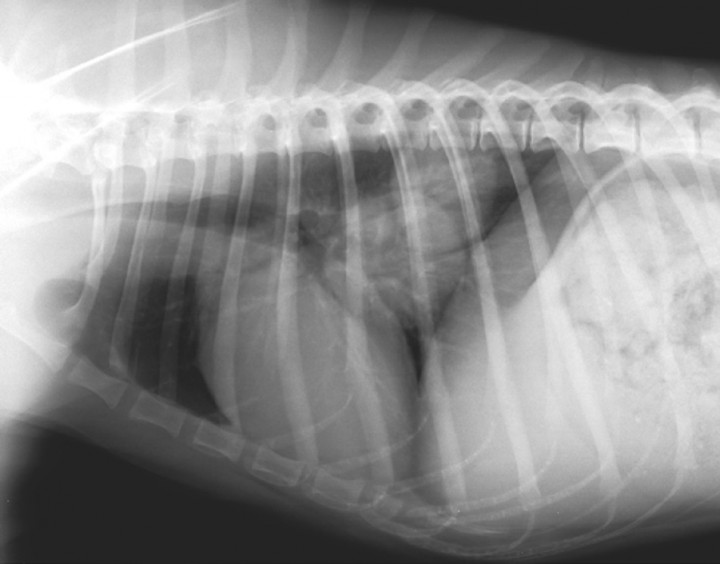

A partir de las lesiones observadas, la mayoría de los casos de la osteopatía hipertrófica están asociados a procesos crónicos torácicos y, menos frecuentemente, a patologías abdominales. Por lo tanto, está indicada la realización de radiografías de la cavidad torácica y abdominal y de ecografía abdominal para buscar la causa subyacente.

En la radiografía lateral derecha de la cavidad torácica (Fig. 7) se observó la presencia de patrón intersticial nodular multifocal en los lóbulos pulmonares caudales, donde se visualizan dos masas bien diferenciadas de forma redondeada con opacidad de tejido blando, contorno regular de 4,5 y 6 cm de diámetro, respectivamente, que se superponen parcialmente. El resto de estructuras se muestran sin alteraciones radiológicas evidentes. Por motivos económicos no se realizaron el resto de proyecciones radiográficas (lateral izquierda y ventrodorsal/dorsoventral) que son necesarias para una correcta localización de las lesiones y para valorar la toma de muestras para el estudio citológico.

<p>Proyección lateral derecha de tórax. Se observa patrón intersticial nodular multifocal en los lóbulos pulmonares caudales donde se observan dos masas bien diferenciadas de forma redondeada con opacidad de tejido blando, de contorno regular de 4,5 cm y 6 cm de diámetro, respectivamente, que se superponen parcialmente.</p>

Proyección lateral derecha de tórax. Se observa patrón intersticial nodular multifocal en los lóbulos pulmonares caudales donde se observan dos masas bien diferenciadas de forma redondeada con opacidad de tejido blando, de contorno regular de 4,5 cm y 6 cm de diámetro, respectivamente, que se superponen parcialmente.

Los hallazgos de las lesiones pulmonares junto con las lesiones óseas conllevan que el diagnóstico más probable sea una osteopatía hipertrófica pulmonar secundaria a un tumor pulmonar.